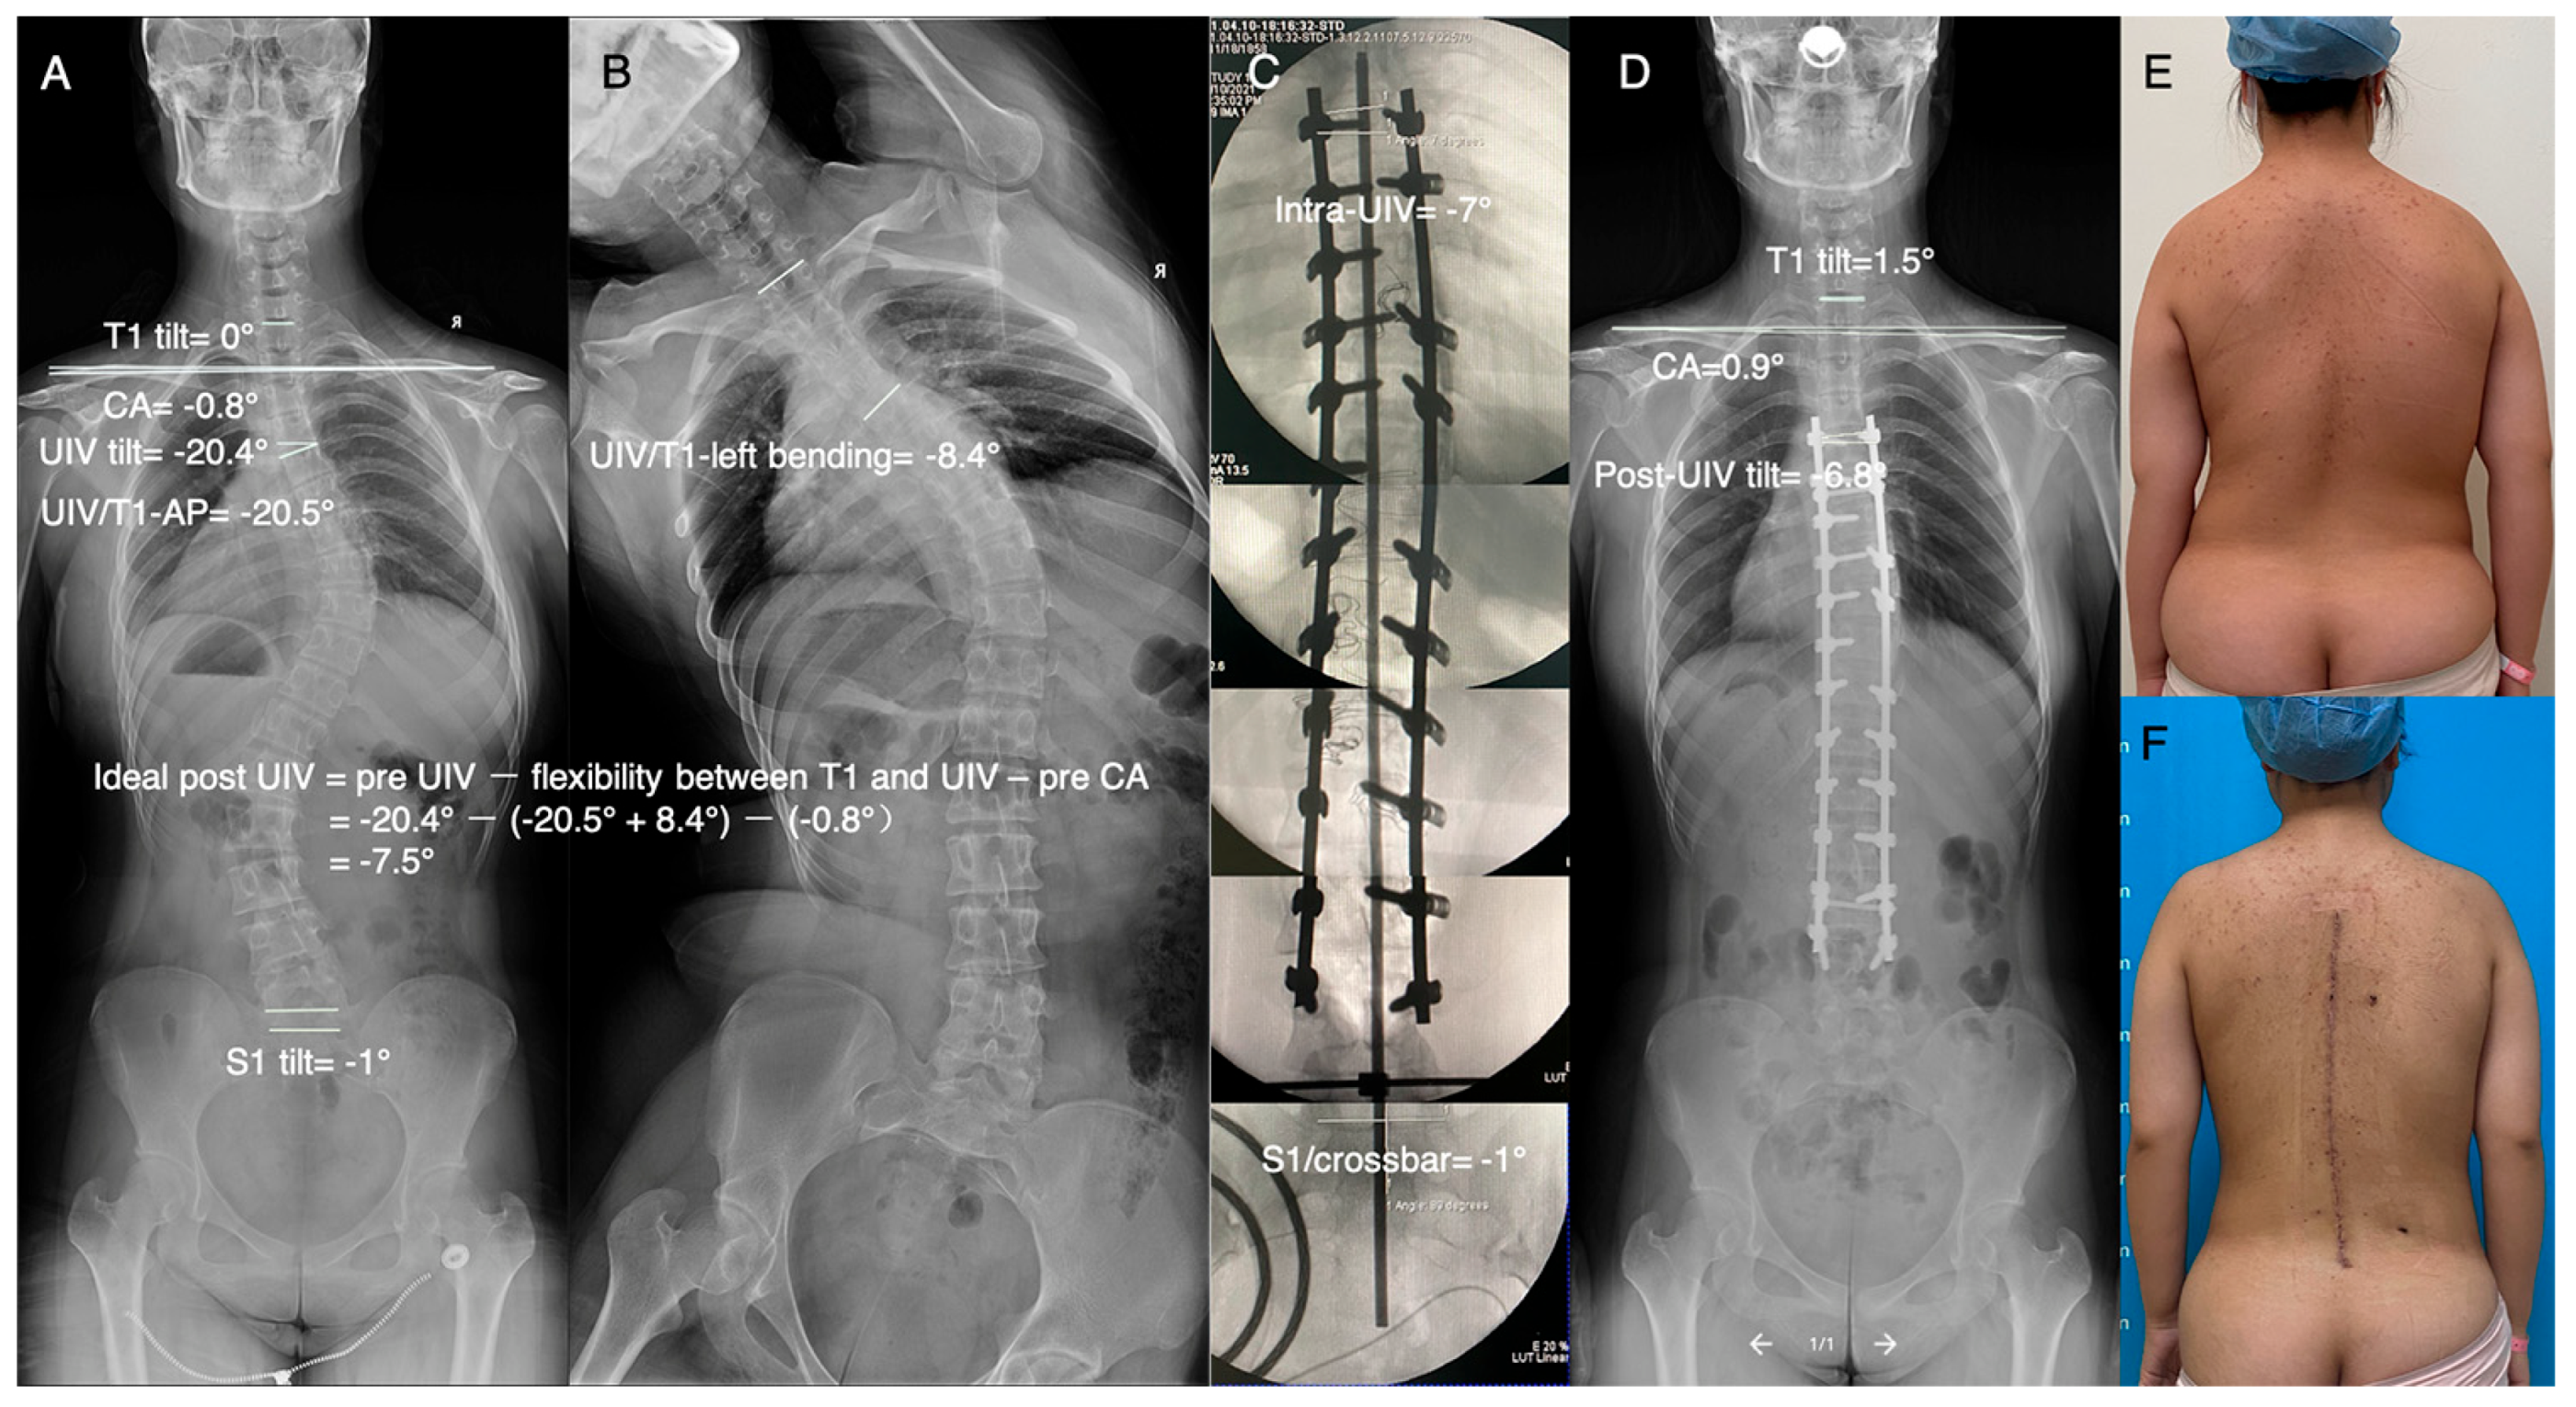

2.4. Verification of the Feasibility of This Method in Clinical Practice